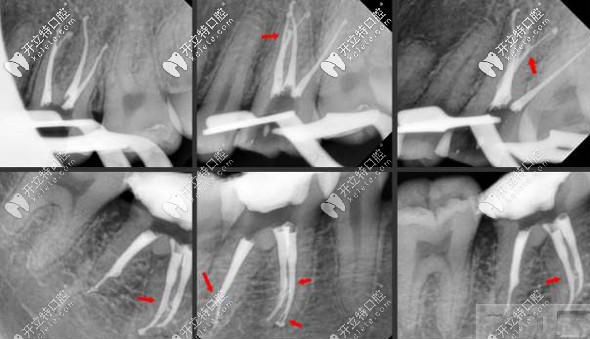

根管治療的拍片圖